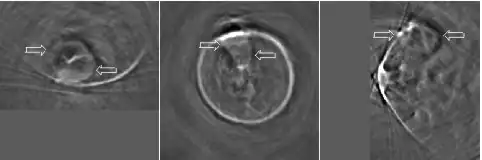

Thermoacoustic imaging was originally proposed by Theodore Bowen in 1981 as a strategy for studying the absorption properties of human tissue using virtually any kind of electromagnetic radiation.[1] But Alexander Graham Bell first reported the physical principle upon which thermoacoustic imaging is based a century earlier.[2] He observed that audible sound could be created by illuminating an intermittent beam of sunlight onto a rubber sheet. Shortly after Bowen's work was published, other researchers proposed methodology for thermoacoustic imaging using microwaves.[3] In 1994 researchers used an infrared laser to produce the first thermoacoustic images of near-infrared optical absorption in a tissue-mimicking phantom, albeit in two dimensions (2D).[4] In 1995 other researchers formulated a general reconstruction algorithm by which 2D thermoacoustic images could be computed from their "projections," i.e. thermoacoustic computed tomography (TCT).[5] By 1998 researchers at Indiana University Medical Center[6] extended TCT to 3D and employed pulsed microwaves to produce the first fully three-dimensional (3D) thermoacoustic images of biologic tissue [an excised lamb kidney (Fig. 1)].[7] The following year they created the first fully 3D thermoacoustic images of cancer in the human breast, again using pulsed microwaves (Fig. 2).[8] Since that time, thermoacoustic imaging has gained widespread popularity in research institutions worldwide.[9][10][11][12][13][14][15] As of 2008, three companies were developing commercial thermoacoustic imaging systems – Seno Medical,[16] Endra, Inc.[17] and OptoSonics, Inc.[18]

- ^ Kruger RA, Miller KD, Reynolds HE, Kiser Jr WL, Reinecke DR, Kruger GA. Contrast enhancement of breast cancer in vivo using thermoacoustic CT at 434 MHz. Radiology 2000;216: 279-283.